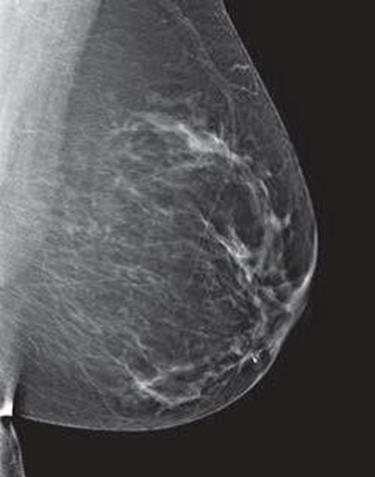

Dense breast tissue, as seen on a mammogram, has more fibrous connective tissue and glandular tissue, and less fatty tissue. It is often inherited, but menopausal hormone therapy, and low body mass index are factors associated with breast density. Dense breast tissue is a risk factor for breast cancer, and a radiologist can tell if a woman has dense breasts.

A mammogram uses X-rays (ionizing radiation) to create images of the inside of the breast to check for cancer and other conditions. It can be used for screening to detect cancer, for instance, before there’s a lump in the breast, or to assist in the diagnosis of cancer. Radiologists use mammograms to interpret, and classify breast density into four categories.

A, B, C, D’s of Breast Density and Mammograms

Dense breasts are common findings after a mammogram, and are not considered a disease, or an abnormal condition. However, they are a risk factor for a woman to develop breast cancer. According to doctors at Memorial Sloan Kettering, women with extremely dense breast tissue “are four to six times more likely to get breast cancer than people with the least dense breasts.”